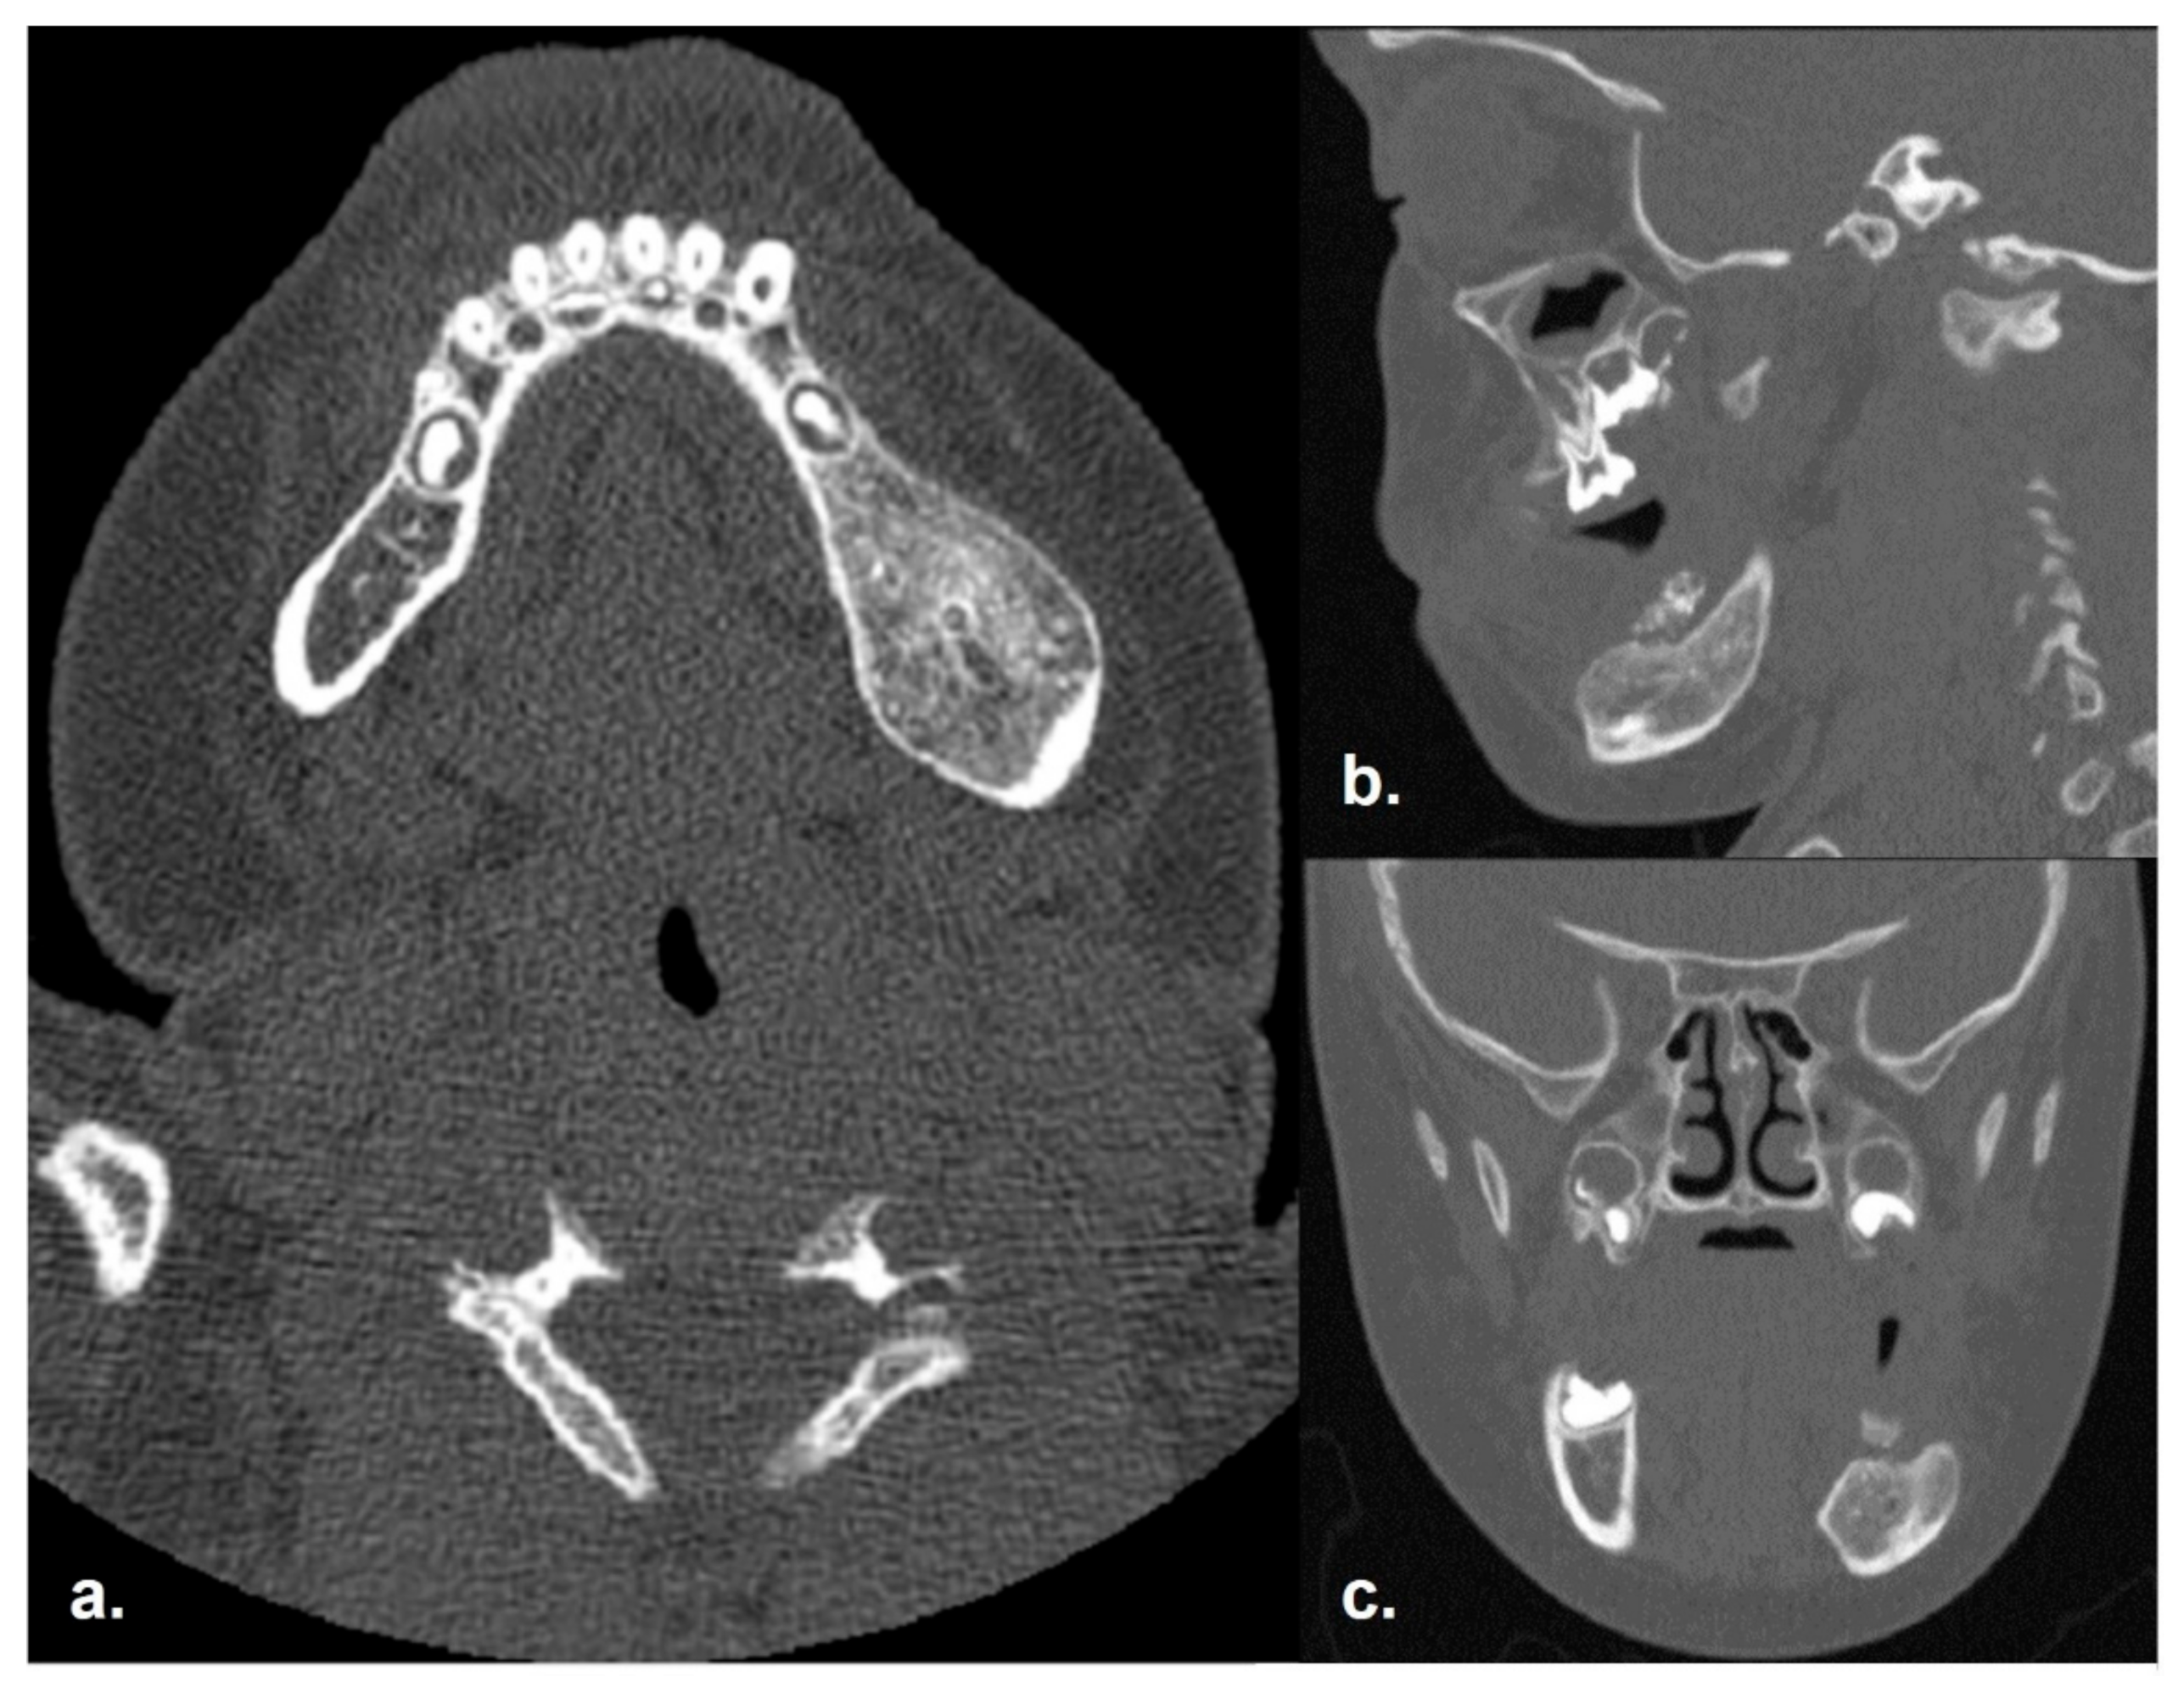

2.1. Clinical and Preoperative Radiological Presentation